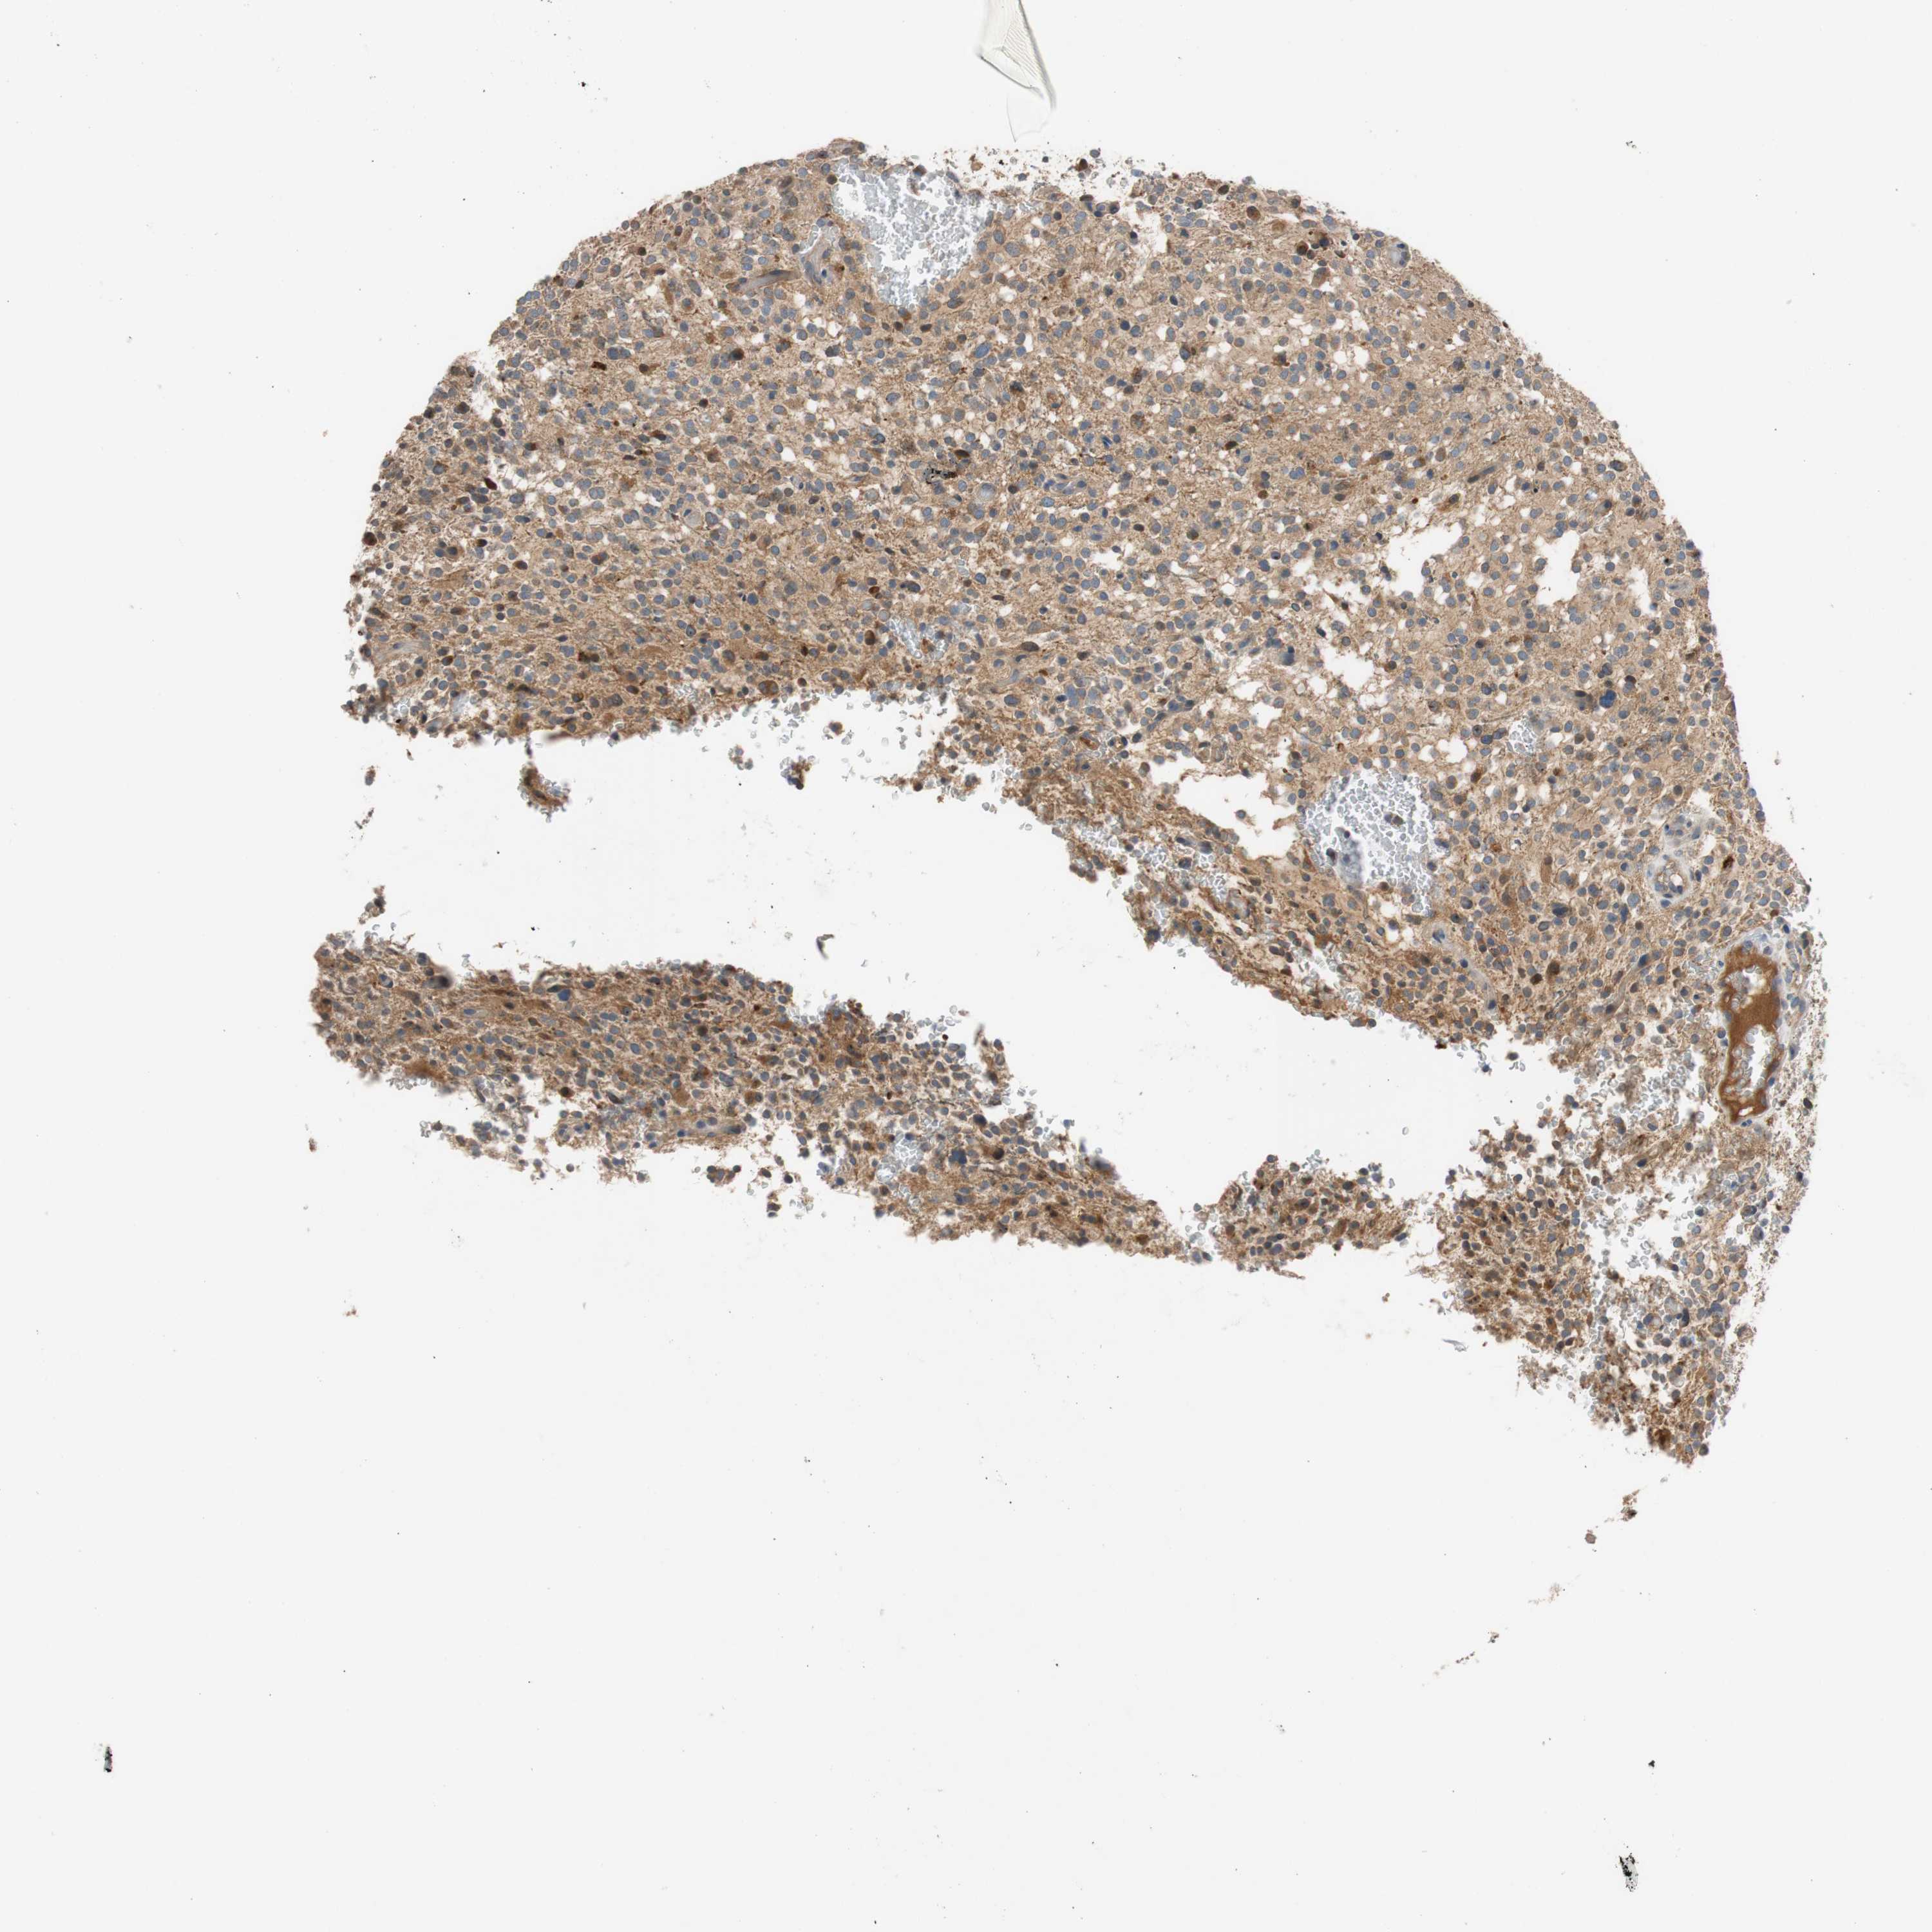

GLIOMA - Protein expressioni

A mouse-over function shows sample information and annotation data. Click on an image to view it in a full screen mode. Samples can be filtered based on level of antibody staining by selecting one or several of the following categories: high, medium, low and not detected. The assay and annotation is described here.

Note that samples used for immunohistochemistry by the Human Protein Atlas do not correspond to samples in the TCGA dataset.

Antibody stainingi

Antibody staining in the annotated cell types in the current human tissue is reported as not detected, low, medium, or high, based on conventional immunohistochemistry profiling in selected tissues. This score is based on the combination of the staining intensity and fraction of stained cells.

Each image is clickable and will lead to virtual microscopy that enables deeper exploration of all samples and also displays staining intensity scores, fraction scores and subcellular localization as well as patient and tissue information for each sample.

HPA046356

HPA048287

HPA050103

CAB009811

CAB032603

Glioma, malignant, Low grade

Glioma, malignant, High grade

Glioblastoma, NOS